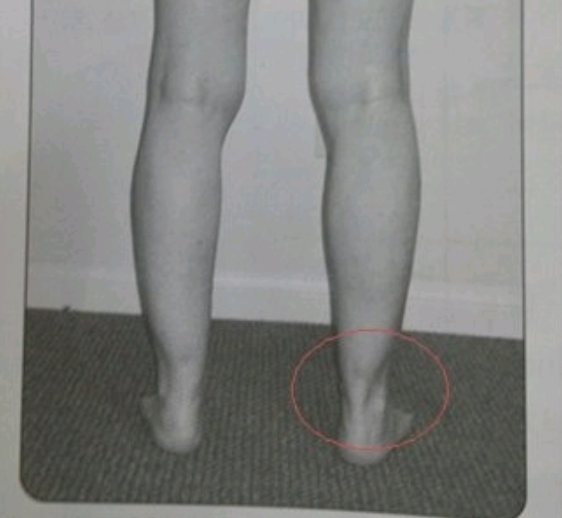

운동을 잘하는 발목과 못하는 발목의 차이는 ‘아킬레스건 길이’라는 게시글의 주장에 네티즌들은 공감하는 반응을 보였다.

이처럼 ‘운동 못하는 발목’에 해당하는 아킬레스건이 짧은 발목을 가진 사람들은 뒷꿈치를 붙이고 쪼그려 앉는 자세가 불가능하다고 알려지기도 했다.